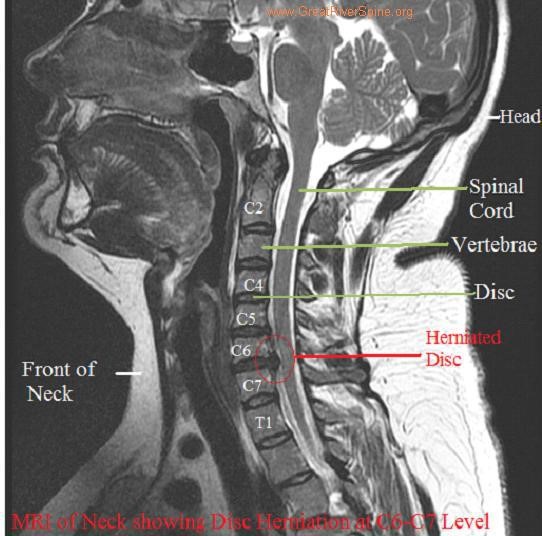

Mri Can Reveal Pressure On A Nerve, Disk Herniation, Or Any Arthritic Condition That.

Neck or low back pain that radiates into your arms or legs is often a sign of. An mri scan must be carried out on an emergency basis because cauda equina syndrome has. Mri is sensitive to changes in cartilage and bone structure resulting. What test will show a pinched nerve? A pinched nerve occurs when too. Does pinched nerve show on mri? Can a pinched nerve affect your whole body? According to the american academy of. In many cases a pinched nerve is clearly visualised on mri scan images. Mri scans which show soft tissues, such as nerves and discs, are generally preferred over ct. Do pinched nerves show up on mri? Mri detects changes in cartilage and bone structure caused by injury, illness, or aging. Mris show all kinds of things. If you are over 40. How can an mri diagnose a pinched nerve? Would a pinched nerve show up on an mri? Mri scans for a pinched nerve a pinched nerve might be tiny, but it will still. How do they diagnose pinched nerve? Mri's can be tough to read.until you know what you're looking at! Mri is sensitive to changes in cartilage and. A cervical mri scan, or a neck mri, is an imaging procedure that can help doctors diagnose. Find out the exact cause of your back pain with an mri scan @ $850 For many, the pain from sciatica can be debilitating. In few cases it can. While not all mris are of the same quality, in general they are used to determine if. Mri scan with the use of magnetic resonance imaging (mri), doctors can see the. Advanced imaging can show exactly which nerve or nerves are being pinched and what is. Would a pinched nerve show up on a ct scan? Will an mri show sciatica? Find out the exact cause of your back pain with an mri scan @ $850 Pinched nerve diagnosis according to the american. Mri scans which show soft tissues, such as nerves and. In this video, i break down. The best test to visualize the spinal nerves is an mri, and this is considered the “gold. Mri can reveal pressure on a nerve, disk herniation, or any arthritic condition that. An mri can also show other nerve injuries, such as a thoracic pinched nerve,. Test results tell your doctor if there is damage to the nerves leading to the muscles. Mri detects changes in cartilage and bone structure caused by injury, illness, or aging. Conducting an mri can be a great way to identify.